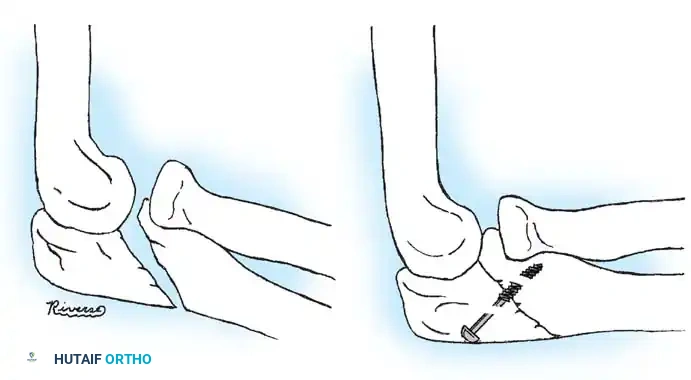

OPEN REDUCTION AND INTERNAL FIXATION (ORIF)

If closed and percutaneous methods fail to achieve <45 degrees of angulation, open reduction is mandated.

Timing: Surgery must be performed within 5 to 7 days of injury. Delayed surgical intervention drastically increases the risk of myositis ossificans and radioulnar synostosis.

Surgical Approach (Kocher Interval)

- Incision: A lateral Kocher incision is utilized, exploiting the internervous plane between the anconeus (radial nerve) and the extensor carpi ulnaris (posterior interosseous nerve).

- Exposure: The joint capsule is incised anterior to the lateral ulnar collateral ligament (LUCL) to prevent iatrogenic posterolateral rotatory instability (PLRI).

- Fixation: Internal fixation is strictly required; periosteal sutures alone are inadequate. Oblique pins across the fracture are preferred.

Surgical Warning: Avoid transcapitellar (transarticular) wires if possible. While technically easier to insert, they carry a high risk of intraarticular breakage and septic arthritis. Merchan and Fowles both reported significant hardware failure rates with transarticular pinning.